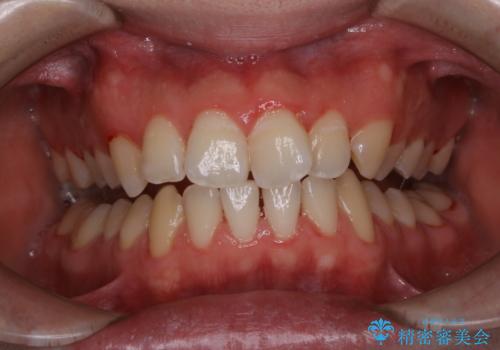

表参道しらゆり歯科 DH西澤

PMTCの注意事項(リスク・副作用など)

- 歯を白くする目的の施術ではありません

- 保険適用外となります